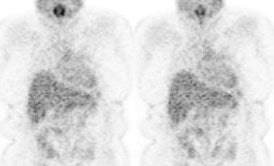

Hyperinsulinemia: The patient below had

a normal glucose level and was injected for an FDG PET

scan. Imaging revealed intense cardiac uptake and a large

about of muscular activity. The findings are consistent

with a hyperinsulinemic state and the patient subsequently

admitted to eating a small breakfast. |